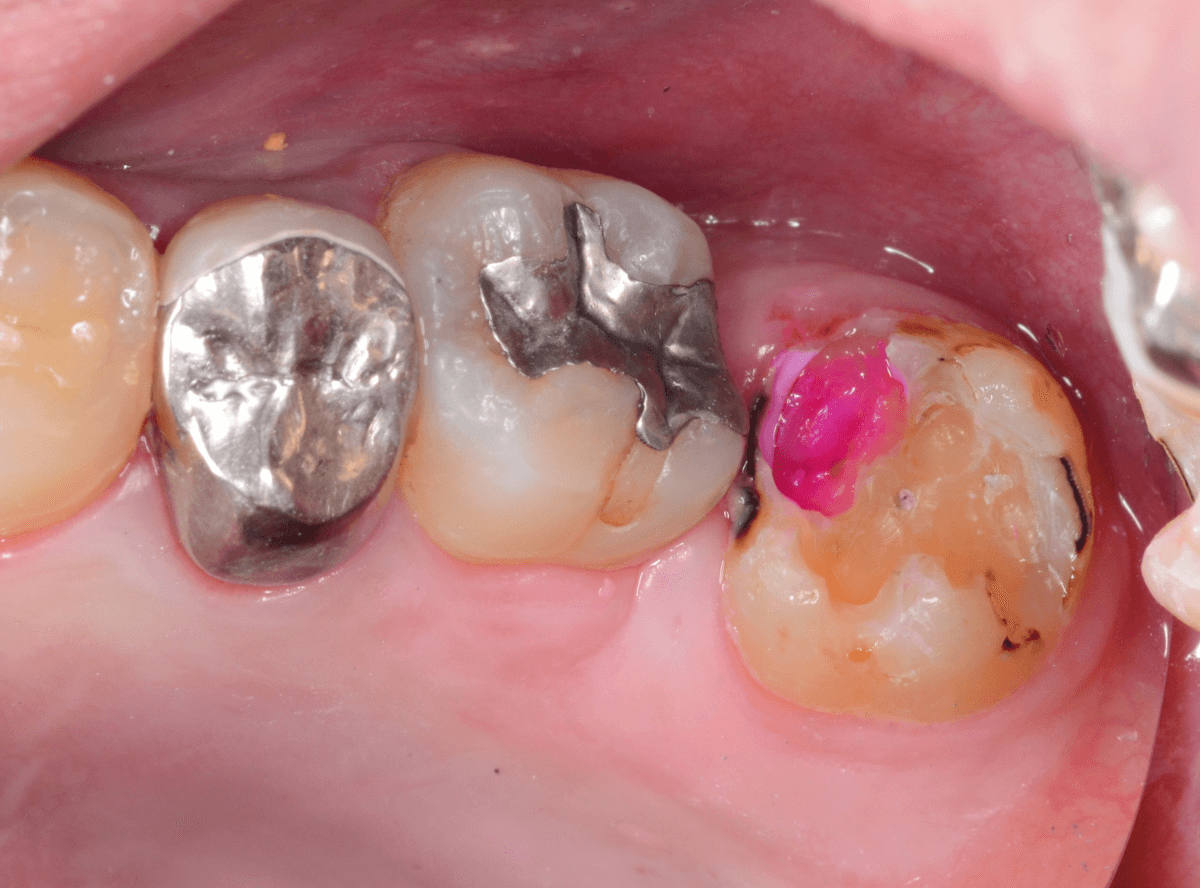

Case.12 検診で見つかった、インレーの下の深い虫歯

検診目的で来院された患者さんです。

特に気になるところもなかったですが、検査をすると、お口の中の色々な部分に虫歯が見つかりました。

その中の一か所、上の奥歯のインレーの下の虫歯です。

見た目だけでははっきりわかりませんでしたが、レントゲン写真で確認すると、インレーの下で虫歯になっているのがわかります。

インレーを除去して、治療を開始します。

ある程度、虫歯を除去したところで、う蝕検知液で確認します。

赤い部分が虫歯です。

やはり、レントゲン写真で確認した部分が深めの虫歯になっていたようです。

全ての虫歯を除去しました。

お薬をつめて痛みやしみが出ないか、しばらく経過観察しますが、おそらく大丈夫でしょう。

症状が出る前に、検診に来ていただいたことで最小限の治療で済みました。